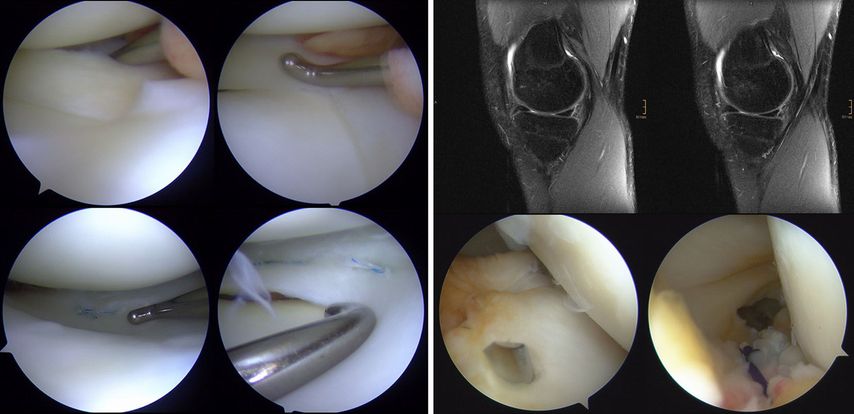

Bei der operativen Versorgung der McKeever-Verletzungen stellt die arthroskopische Versorgung heute den Goldstandard dar. Abhängig von der Fragmentgröße und -form stehen mehrere Fixationsmethoden zur Verfügung, die arthroskopisch, arthroskopisch assistiert oder auch offen durchgeführt werden können. Bei der arthroskopischen Reposition mit transossärer Auszugsnaht mit resorbierbarem Nahtmaterial ist ein Zweiteingriff zur Materialentfernung nicht erforderlich und die Schädigung der Wachstumsfuge ist minimal (Abb. 4).

Abb. 4: Schematische Darstellung und arthroskopische Bilder bei McKeever-Verletzung: Nach Reinigung des Frakturbetts und Reposition des Fragments erfolgt eine zweifache transossäre Auszugsnaht mit resorbierbarem Nahtmaterial (mod. nach Stotter und Reuter 2022)44